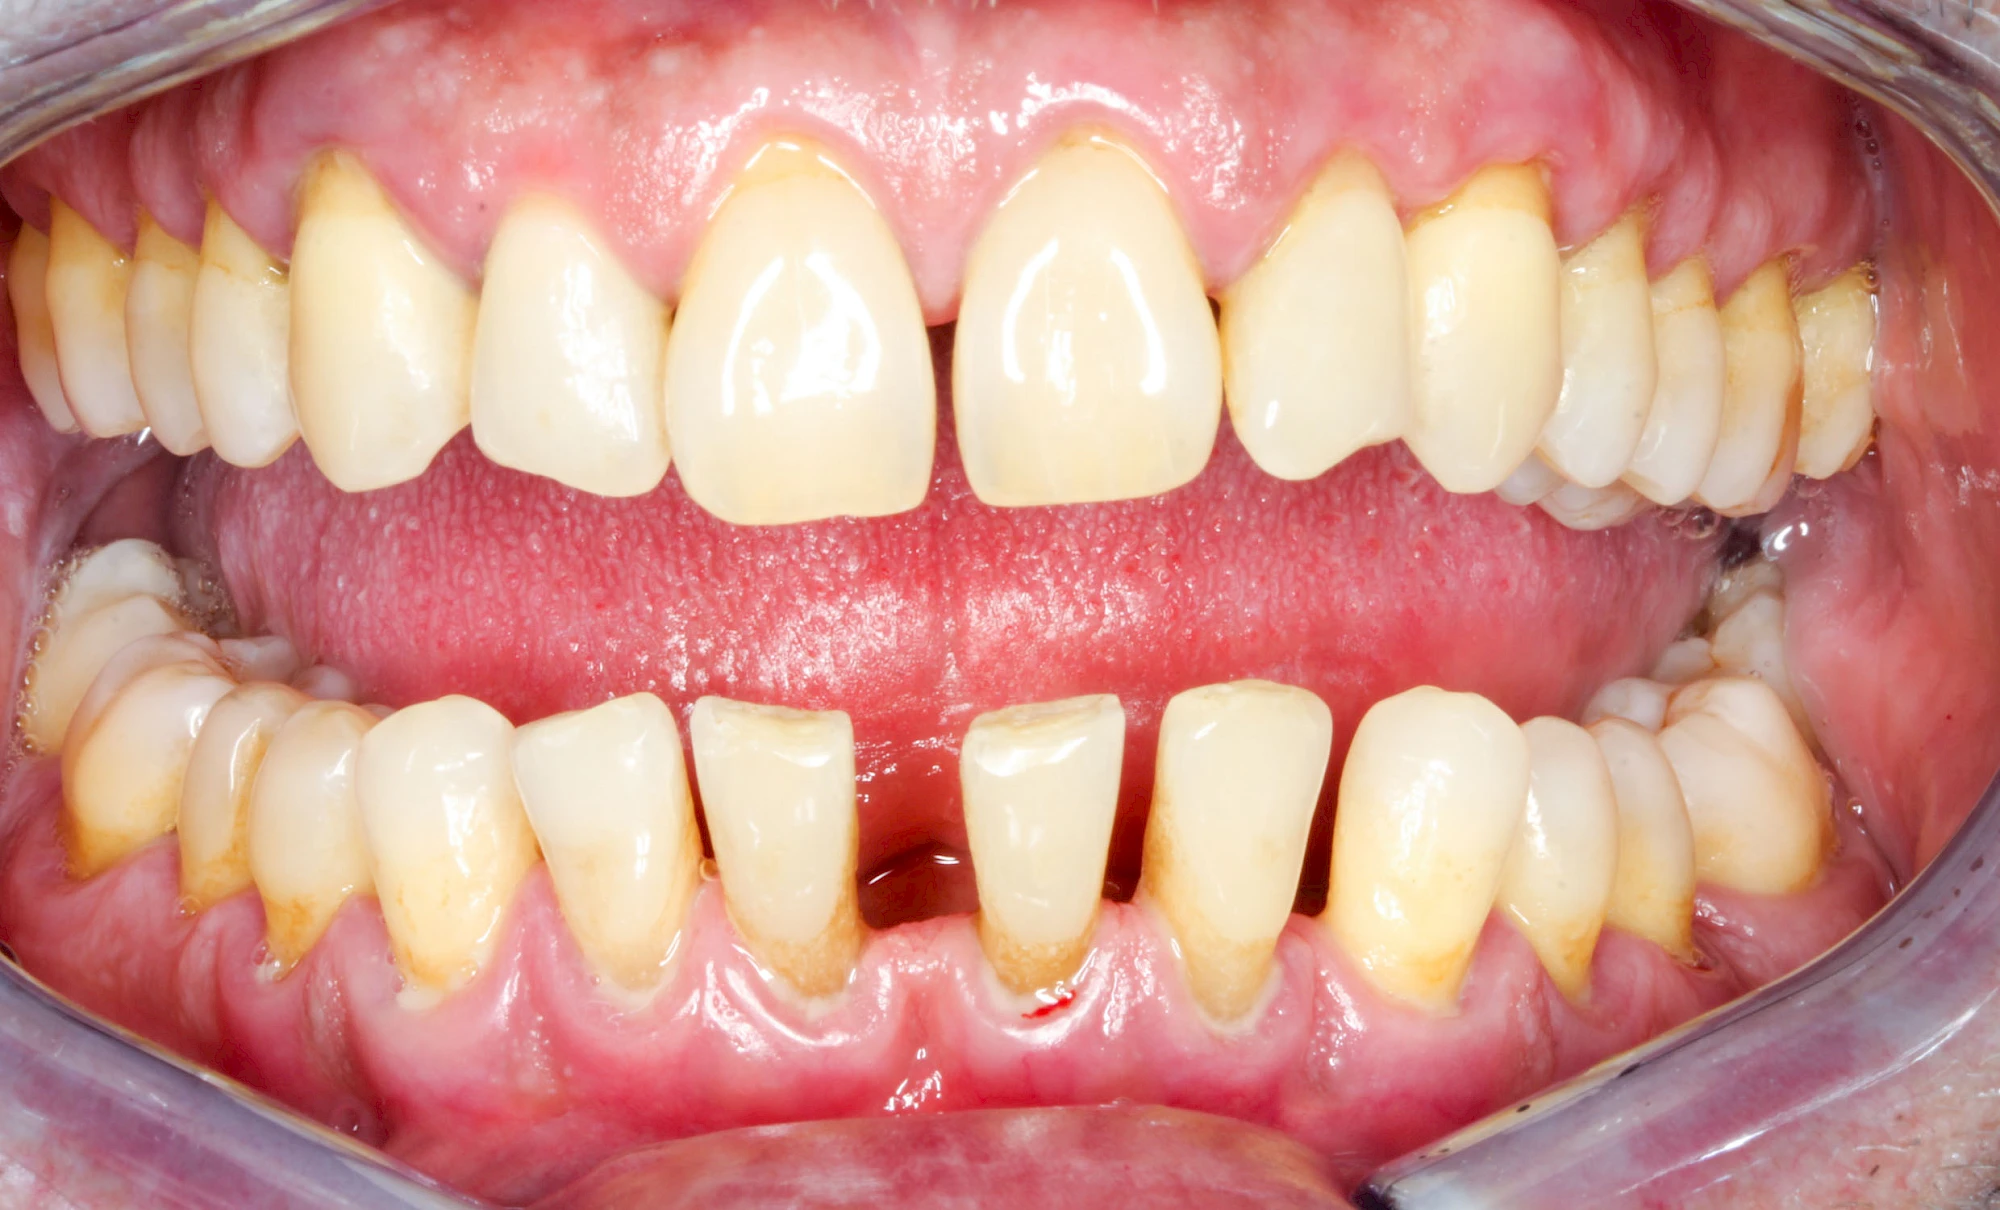

Ist zunächst nur das Zahnfleisch von der Entzündung betroffen, spricht man von Gingivitis. Später, wenn auch der Knochen um die Zähne herum entzündet ist, spricht man von einer Parodontitis. Bei der Parodontitis wird der Knochen nach und nach abgebaut und das Zahnfleisch zieht sich zurück. Die Zahnhälse und Zahnwurzeloberflächen liegen mehr und mehr frei. Die Zähne werden zunehmend lockerer und fallen schließlich aus.